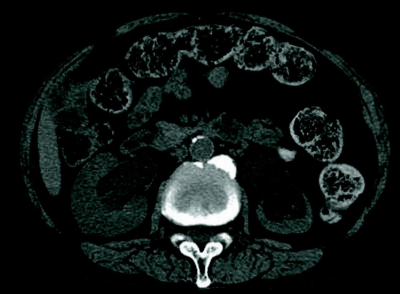

血液所見:赤血球 382万、Hb 11.1 g/dL、Ht 35%、血小板 10万。血液生化学所見:アルブミン 3.2 g/dL、総ビリルビン 1.3 mg/dL、AST 38 U/L、ALT 42 U/L、LD 230 U/L(基準 120〜245)、尿素窒素 40 mg/dL、クレアチニン 2.8 mg/dL、Na 132 mEq/L、K 5.6 mEq/L、Cl 98 mEq/L、CEA 7.8 ng/mL(基準 5以下)、CA19-9 69 U/mL(基準 37以下)。CRP 2.1 mg/dL。腹部超音波検査で膀胱内に尿を認めない。胸部エックス線写真で心胸郭比 56%。腹部単純CTを別に示す。